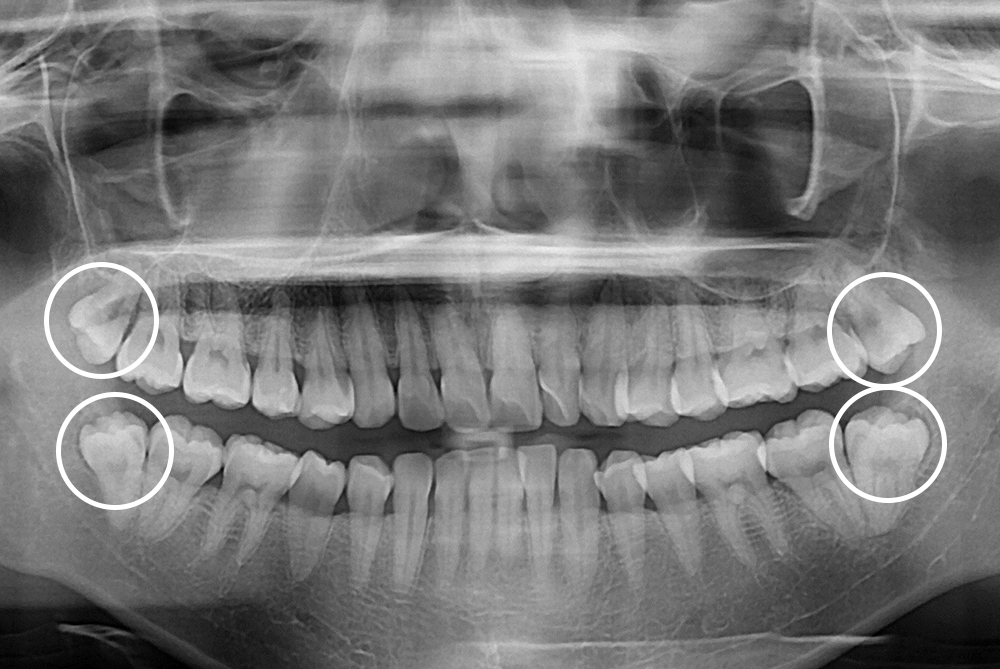

[사랑니] 매복 사랑니 발치

치료전 : 2018-09-19